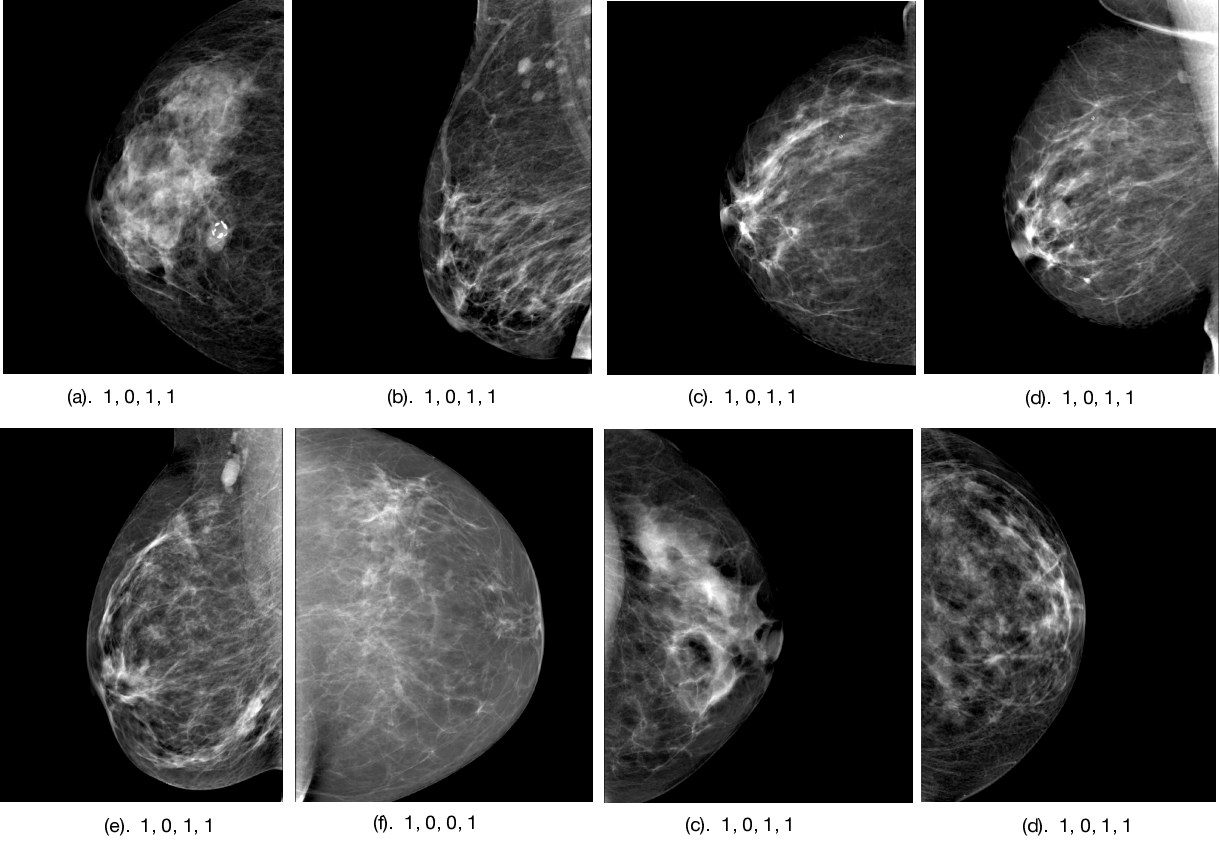

We further analyze this most successful classifier’s results before and after adding the radiologist gist response to the input vector. We notice interesting trends when comparing the radiologists’ decisions to the classifier’s decisions. The classifier utilizing both the deep features and the radiologist gist input manages to correct 8 of the 16 false negative errors that the radiologists made, while only introducing three false positives and one false negative. On the other hand, after introducing the radiologist gist input to the classifier, 25 errors made by the classifier without gist response input are corrected, with only three errors introduced. These corrections include 8 false negatives and 17 false positives. There are also 5 instances in which both the classifier and the radiologists make the same mistake (see Supplementary materials for these image samples). In this same case, we see an improvement over the classifier not utilizing radiologist gist response, increasing AUC from 0.681( CI [0.558, 0.789]) to 0.899( CI [0.823, 0.962]). One-way Welch’s F test shows a statistically significant main effect of the classifier on the AUC ( = , ). A Games-Howell post-hoc test revealed that the AUC of the classifier without gist input is statistically significantly lower than the radiologists’ gist response (0.679 +/- 0.0597, ), and that the classifier with gist input was statistically significantly higher than the radiologists’ gist response(, ).

Figures 4, 5, and 6 show the imaging for which both humans and CNNs make mistakes, model introduced errors, and model corrected human errors. Figure 7 shows the receiver operating characteristic curve (ROC curve) for each of the 16 end-to-end models between the CNNs and radiologist gist plus CNNs. Tables 1 and 2 show the AUC data and differences used in the main text from the 16 conditions we have tested. Although the present work provides knowledge about adding radiologists’ data into CNN, it does not allow for training on new data, thus restricting our application domain to a small range of in-house data.